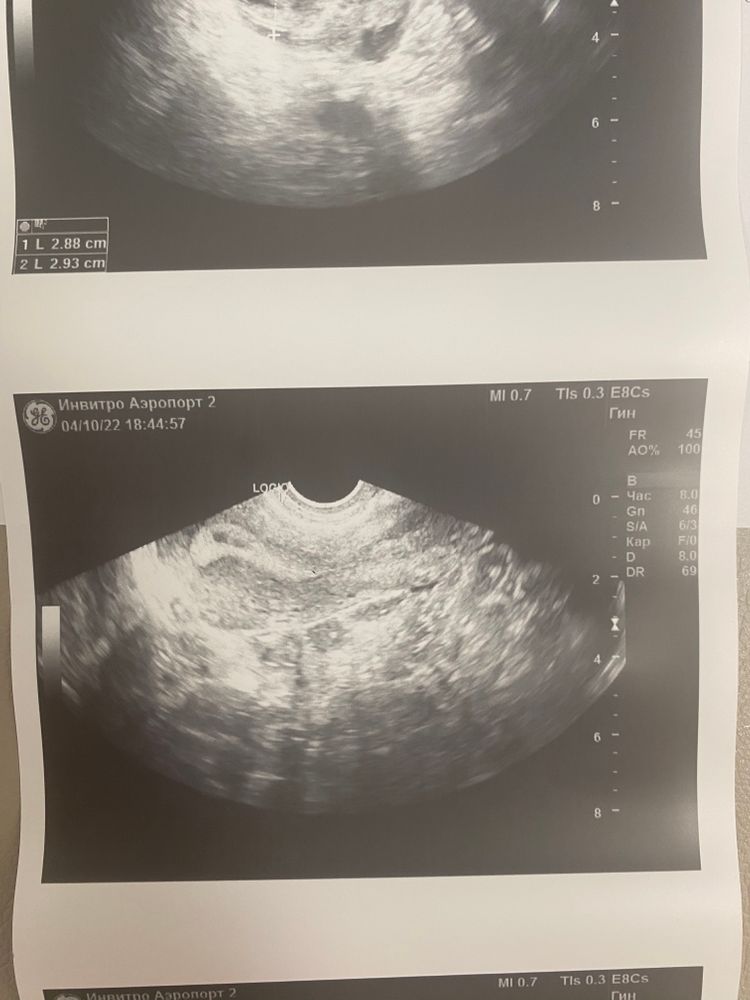

Вчера был 26 ДЦ( мой цикл 36 дней) овуляцию не отслеживала . сделала узи так как вторую неделю тянул правый бок. Окопалась киста желтого тела и еще что то не понятное в матке. Врач сказал либо придут месячные завтра после завтра либо это беременность. Сказал пока ждать. Скажите пожалуйста , а что видите вы на снимках. Заключаете врача прикрепляю

Не знаю что это,но эндометрий точно не впорядке, какое-то образование...в заключении узист тоже пишет ,киста эндометрия (признаки). Беременность ,если и есть,то пока не видно ,очень рано еще.

Оксана, вообще эндометрий еще толстенький ,2й фазы. Перед месячными он сдувается,а в беременность наоборот растет. Пока не понятно